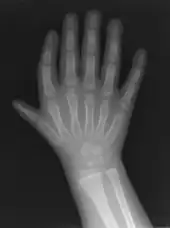

| Triphalangeal thumb | |

| Finger-like appearance | |

Triphalangeal thumb (TPT) is a congenital malformation where the thumb has three phalanges instead of two. The extra phalangeal bone can vary in size from that of a small pebble to a size comparable to the phalanges in non-thumb digits. The true incidence of the condition is unknown, but is estimated at 1:25,000 live births.[1] In about two-thirds of the patients with triphalangeal thumbs, there is a hereditary component.[2] Besides the three phalanges, there can also be other malformations. It was first described by Columbi in 1559.[3]

The triphalangeal thumb has a different appearance than normal thumbs. The appearance can differ widely; the thumb can be a longer thumb, it can be deviated in the radio-ulnar plane (clinodactyly), or thumb strength can be diminished. In the case of a five-fingered hand it has a finger-like appearance, with the position in the plane of the four fingers, thenar muscle deficiency, and additional length. There is often a combination with radial polydactyly.